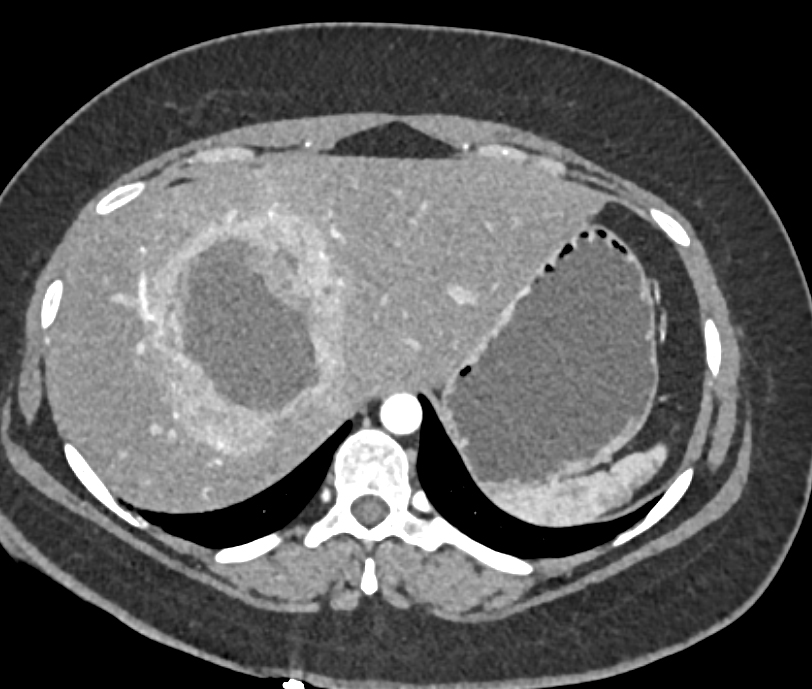

The least likely diagnosis in this case is

necrotic hepatoma

metastatic neuroendocrine tumor

primary neuroendocrine tumor

hemangioma